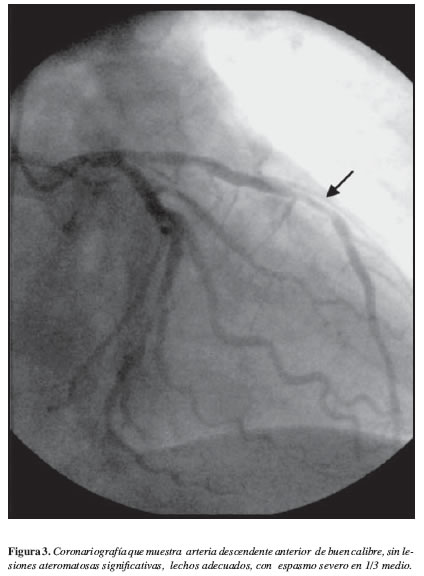

Al segundo día del evento se realizó cateterismo cardiaco, coronariografía y ventriculograma (Figura 3) encontrando arteria descendente anterior de buen calibre, sin lesiones ateromatosas significativas, lechos adecuados, espasmo severo en 1/3 medio que cedió con nitroglicerina intracoronaria; arteria circunfleja de buen calibre, con lesión suboclusiva en tercio distal a la cual se le colocó stent de 3.0 x 16 mm quedando con buen resultado angiográfico y flujo TIMI III. Ventriculograma con aquinesia anterior y apical, y función sistólica severamente deteriorada, con FE: 30%. El paciente evolucionó satisfactoriamente por lo que se trasladó al área de hospitalización donde continuó su tratamiento sin complicaciones hasta su alta médica.